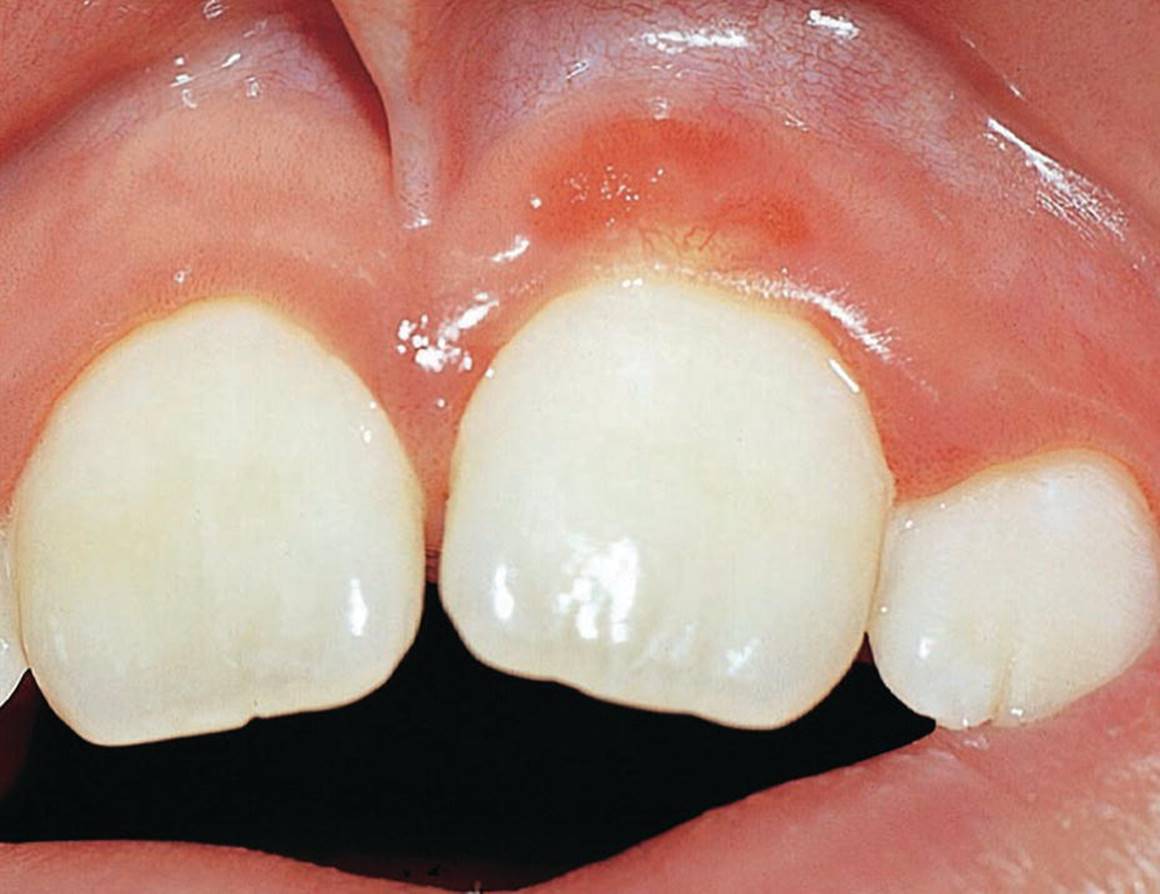

Eruption cysts

Eruption cysts may be defined as dentigerous cysts located in the soft tissues. If there is bleeding in the cyst, it is classified as en eruption hematoma. The cyst can occur in very young children, but is more commonly found in connection with tooth eruption. Usually, there is a small, smooth swelling in the gingival tissues at the site of the erupting tooth. If treatment is indicated, marsupialization is the treatment of choice. The tooth will then erupt rapidly.